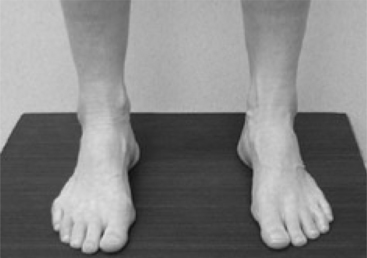

Muscles become weak when they maintain a lengthened position, particularly when the stretch occurs during periods of prolonged rest. A common example is the development of elongated dorsiflexor and shortened plantar flexor muscles in the patient for whom bed rest is prescribed or in the individual who remains supine for a prolonged period without the use of a footboard. This problem is exaggerated when the sheet exerts a downward pull on the feet, causing an additional force into plantar flexion and a consequent lengthening of the dorsiflexor muscles.

Another example is the prolonged stretch of the posterior gluteus medius that occurs while sleeping. This condition is seen particularly in the woman with a broad pelvis who regularly sleeps on her side with her uppermost leg positioned in adduction, flexion, and medial rotation. During manual muscle testing, this patient is unable to maintain the hip in abduction, extension, and lateral rotation—the testing position—or at any point in the range, as the resistance is continually applied by the examiner. The resultant lengthening of the muscle can produce postural hip adduction or an apparent leg length discrepancy when the patient stands.